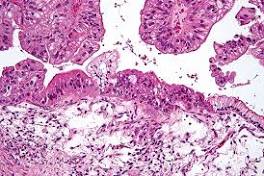

Cells Can Follow a Gene-Flaw-Free Path to Cancer Ovarian cancer can arise through fluctuations in the expression levels of competing intracellular proteins, absent extracellular stimulation or mutation.